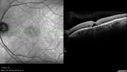

60-year-old man has juxtafoveal retinal telangiectasis in both eyes with vision change. Recently his vision has been declining. He had more trouble reading. I last saw him in March of 2010. Since then he notices he is not as good as he was.

VISUAL ACUITY: OD 20/50, OS 20/70. IOP: OD 11, OS 12. The posterior chamber intraocular lens is in good position in both eyes.

OS: Vertical C/D ratio is 0.5. There is no posterior vitreous separation. There is hemorrhage in the macula with pigment epithelium thickening superonasal to the fovea.

SPECTRALIS-SD-OCT SCAN: The OCT scan of the right eye shows a normal central foveal thickness of 289 microns and the left eye shows foveal edema with juxtafoveal edema. The average central foveal thickness was 330 microns. (NOTE: Retinal thickness measured with Spectralis OCT is approximately 70 μm greater than that measured with Stratus OCT. This increased measurement corresponds to the inclusion of the outer segment-RPE-Bruch's membrane complex by Spectralis OCT.) Photos confirm clinical findings.

1. JUXTAFOVEAL RETINAL TELANGIECTASIS – BOTH EYES

2. STAGE FIVE – LEFT EYE

3. WET AGE-RELATED MACULAR DEGENERATION – LEFT EYE

DISCUSSION: I explained to the patient with Avastin there is a chance of drying the macula in the left eye and improving the vision. I treated the left eye with intravitreal injection of Avastin (1.25 mg/0.05 ml) without any difficulty today.